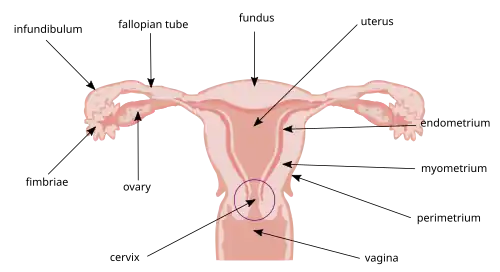

Camadas

As camadas do útero, da mais interna para a mais externa, são as seguintes:

| Camada | Descrição |

| endométrio | camada vascularizada (ciclo menstrual) |

| miométrio | (camada muscular) O útero consiste principalmente de tecido muscular liso, conhecido como miométrio. |

| perimétrio | (camada serosa) O tecido frouxo que o envolve é chamado de perimétrio. |

| peritônio | O útero é envolvido pelo peritônio. |

Vista frontal esquemática da anatomia feminina

Vista frontal esquemática da anatomia feminina -